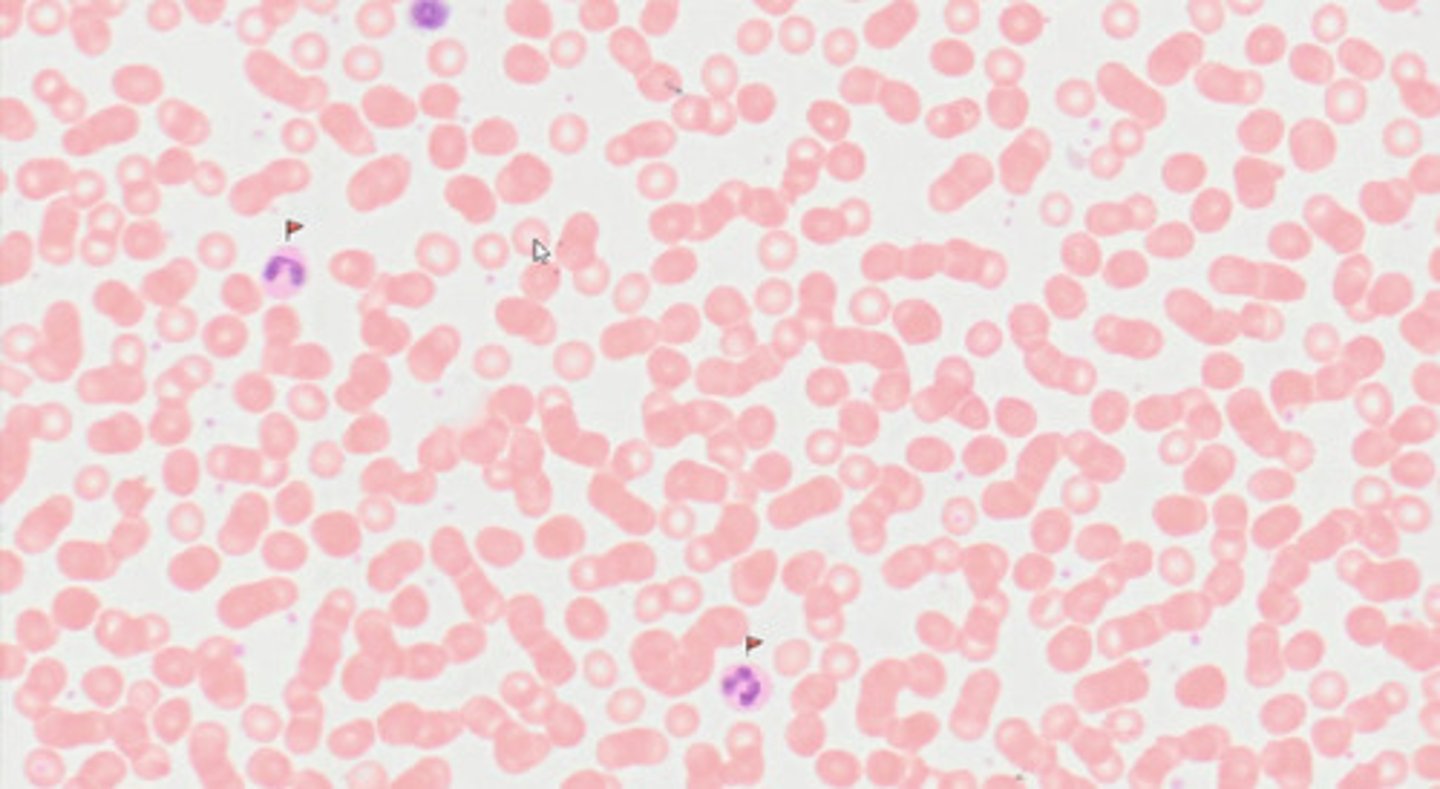

Rozmaz krwi ludzkiej (met. Pappenheim)